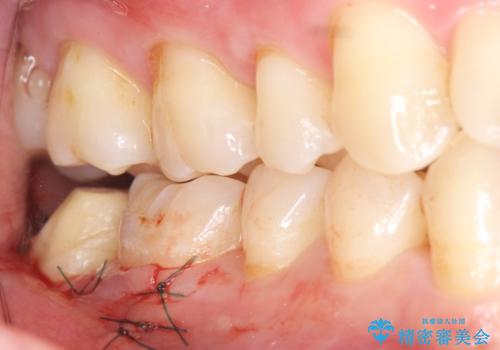

銀歯を除去し、歯周外科処置(右下7遠心の骨整形及びディスタルウェッジ)を行った後にメタルボンドクラウンによる補綴を行いました。

歯周外科処置(右下7遠心の骨整形及びディスタルウェッジ)により、深部に及ぶう蝕を除去するとともに歯肉縁上の健全歯質を獲得でき、適合の良い被せ物を作製することができました。

被せ物の種類:右下6 e-max press セラミックインレー

右下7 メタルボンドクラウン エコノミー